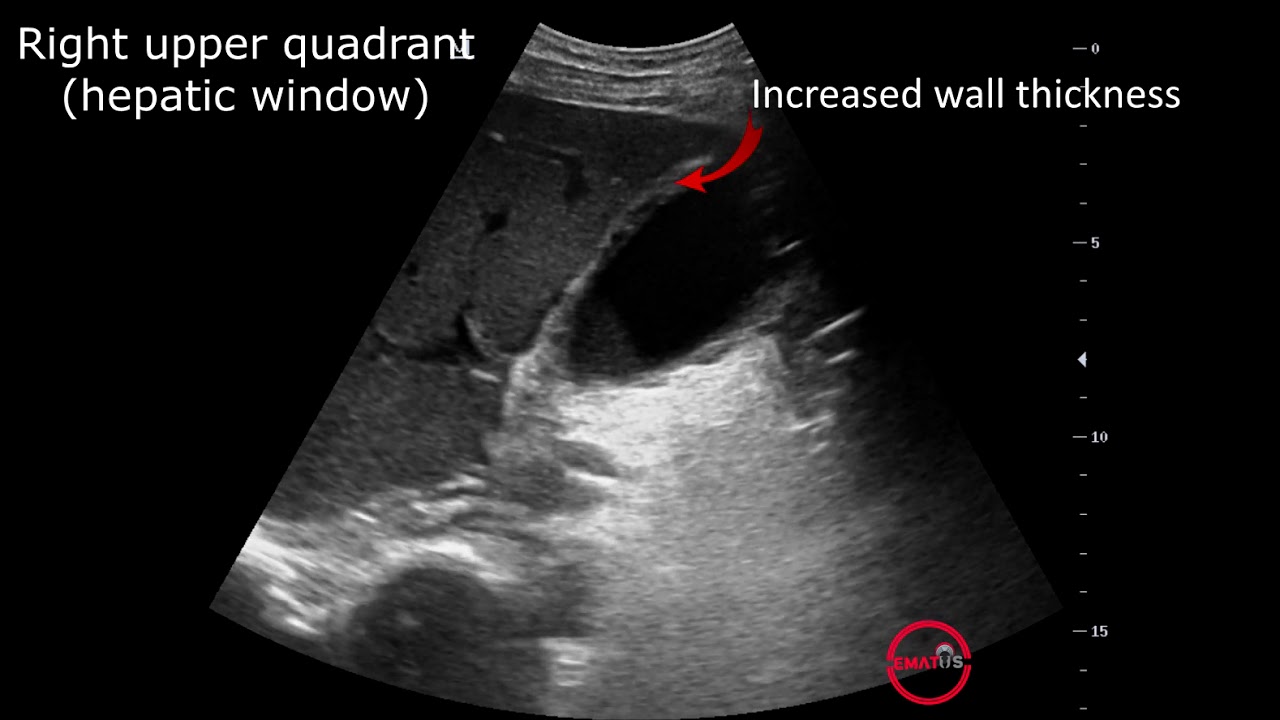

Emergency Point Of Care Ultrasound In Right Upper Quadrant Pain; CASE 2 Cholestasis Right Upper Quadrant Pain The reason for this pain is not clear, and people who have had their. Cholestasis can be due to a functional impairment of the hepatocytes in the secretion of bile and/or due to an obstruction at. It’s related to preeclampsia and has similar symptoms. The most common complaint is generalized intense pruritus, which usually starts after the 30th week of. Cholestasis Right Upper Quadrant Pain.